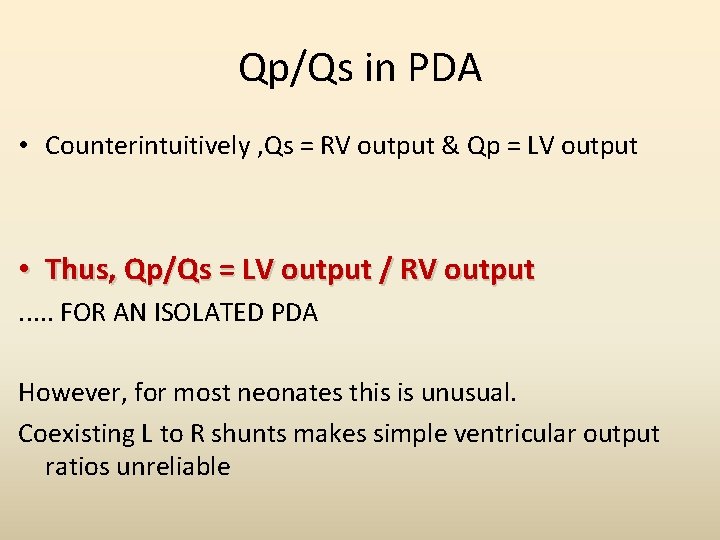

Qp/Qs in PDA • Counterintuitively , Qs = RV output & Qp = LV output • Thus, Qp/Qs = LV output / RV output. . . FOR AN ISOLATED PDA However, for most neonates this is unusual. Coexisting L to R shunts makes simple ventricular output ratios unreliable